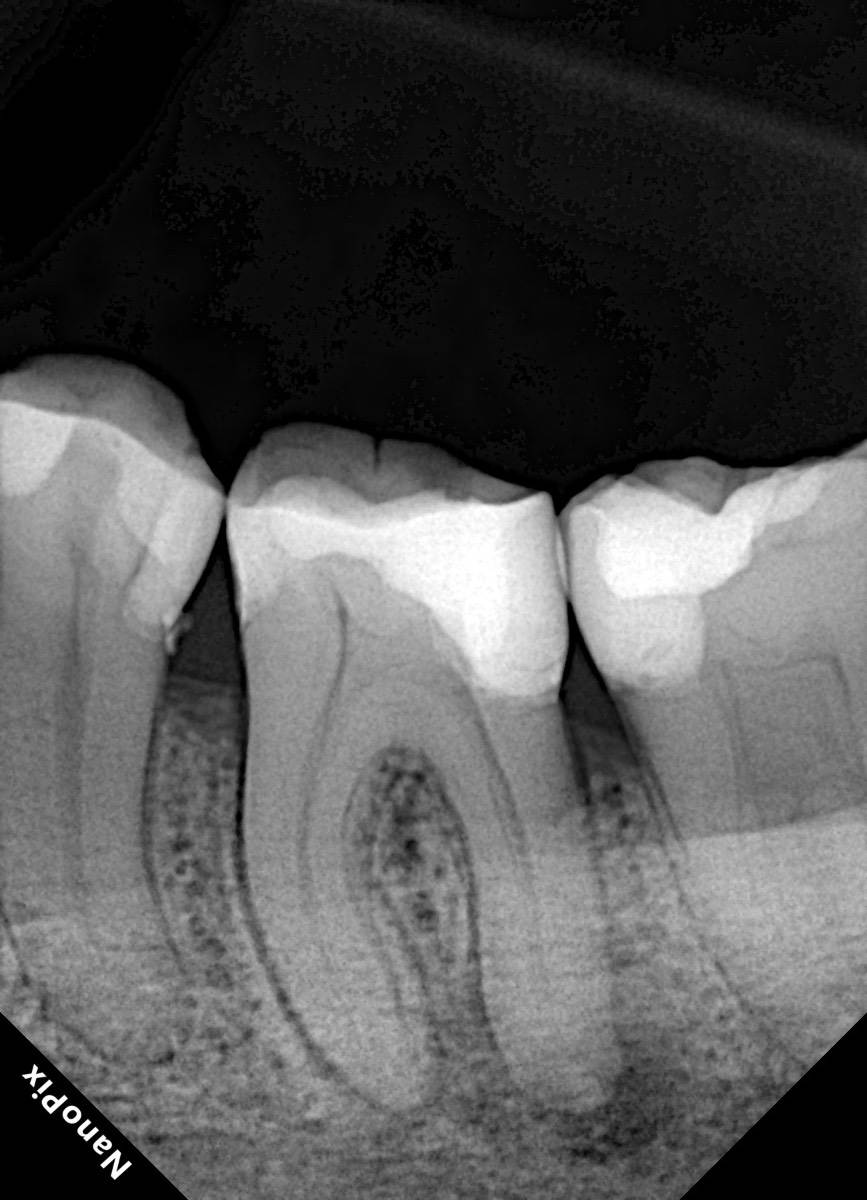

Гарриевич Опубликовано 10 часов назад Автор Поделиться Опубликовано 10 часов назад Еще один осмотр спустя 3 года и полное заживление 1 Ссылка на комментарий

Doc Опубликовано 46 минут назад Поделиться Опубликовано 46 минут назад 9 часов назад, Гарриевич сказал: Еще один осмотр спустя 3 года и полное заживление Круто, как обычно! Ссылка на комментарий